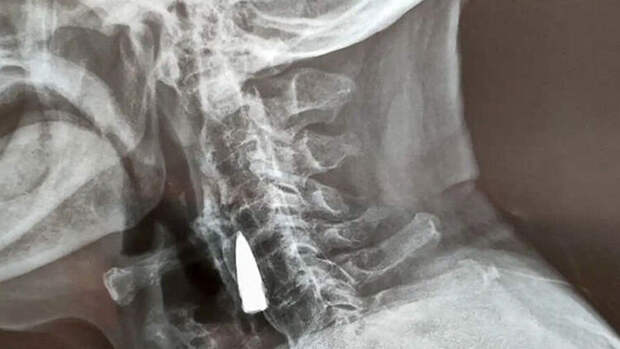

Чжао Хэ пожаловался семье на дискомфорт в шее. Родственники отвезли мужчину в больницу, где ему сделали рентген, чтобы узнать, что могло быть источником боли.

Только вместо этого врачи с удивлением обнаружили там пулю, посмотрев снимок пациента."Он был ранен, когда во время одного из боев переправлял через реку раненого товарища. Осколки есть и в других частях его тела", - рассказал зять китайца.

Сам Чжао считает, что пуля находится в его шее с 1944 года. Снаряд пробил ему верхнюю челюсть и выбил несколько зубов, после чего застрял рядом с горлом. Проведя совещание, медики решили, что патрон лучше не доставать - рядом находится много кровеносных сосудов. Ветеран согласился с этим решением.